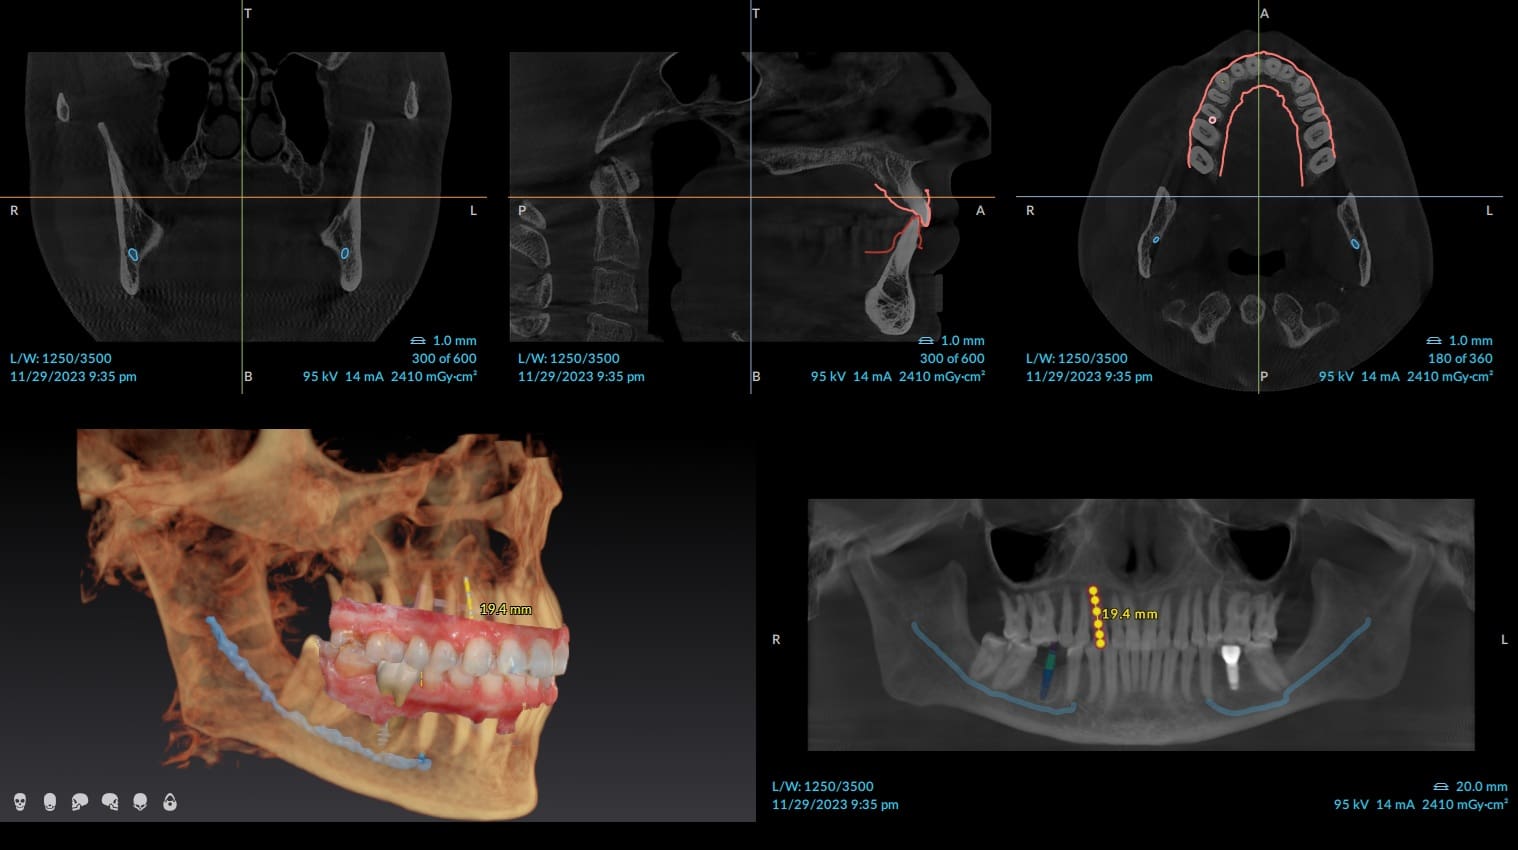

Unlike traditional two-dimensional dental X-rays that compress anatomy into a flat image, cone beam technology produces a full volumetric 3D scan. This enables visualization of bone density, tooth positions, nerve pathways, sinus anatomy, root structure, infections, fractures, cysts, airway dimensions, and implant sites from every angle.

3D Cone Beam CT, commonly referred to as CBCT (cone beam computed tomography), uses a cone-shaped X-ray beam that rotates around the head once to capture hundreds of images in seconds. Specialized software then reconstructs these images into a high-resolution three-dimensional model of the oral and maxillofacial structures.

Because the anatomy is viewed in true spatial relationships, treatments are planned with far fewer uncertainties.